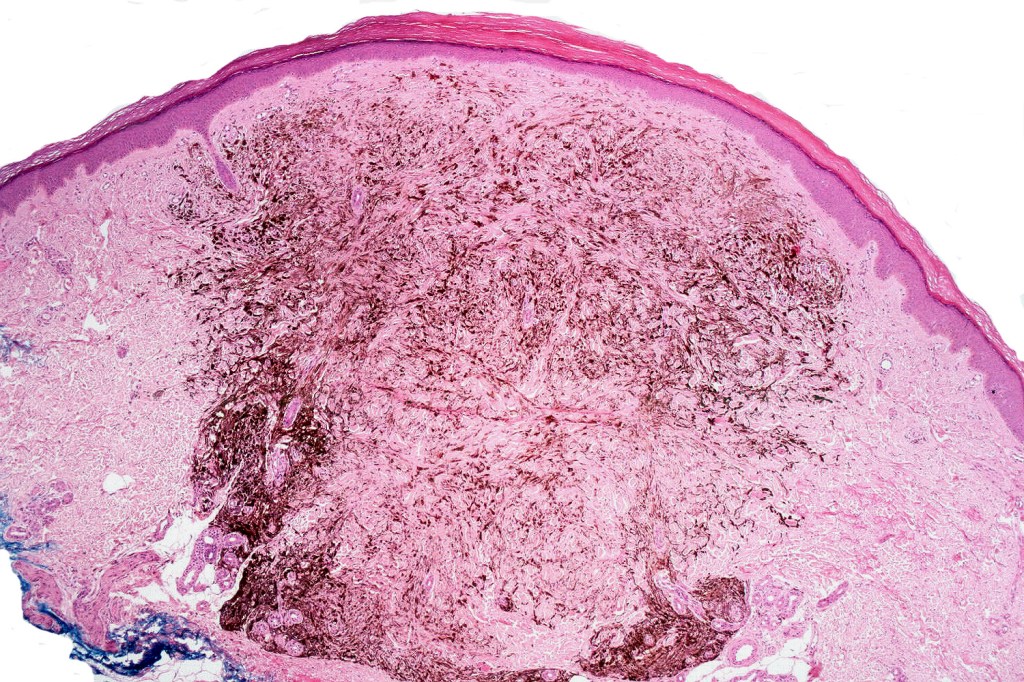

Cellular blue nevus

This uncommon most often devlops on the buttocks, sacrococcygeal region & distal extremities although it may be seen at just about any site. It shows a predilection for females and is diagnosed most often in the 2nd-4th decade. It presents as a blue-black/ or black nodule measuring 1-2 cm in dianeter. Similar to common blue nevus, the cellular variant can be encountered in a wide range of non-cutaneous locations.

Histological features

•Most characteristic is the dumbbell silhouette although a plague morphology may also be encountered

•Admixture of spindle cells, pigmented bipolar or dendritic cells & melanophages

•An alveolar pattern is characteristic particularly with clear cell nodules

•Stromal fibrosis, myxoid change, vascular hyalinization with cyst formation are often seen